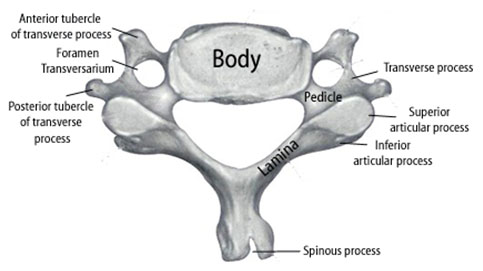

For the C3-C6 cervical vertebrae, general specific bony characteristics exist (Figure 5). Each vertebra consists of a body, transverse processes, and associated anterior and posterior tubercles, articular processes (i.e. lateral masses), groves for spinal nerves, pedicles, laminae, and spinous process. The transverse processes consist of anterior and posterior tubercles. The tubercles are connected by a sulcus of bone which the vertebral artery passes through the foramen transversarium and the corresponding spinal nerve root exits.[10] The cervical nerve roots exit through the neural foramen above their corresponding cervical vertebral body (i.e. the C6 cervical nerve root exits between C5 and C6) except for C8 nerve root which exists between C7 and T1. As the nerve roots exit the foramen they often divide into 2 or 3 divisions.[11]

Figure 5. Illustration showing the relevant anatomy of a cervical vertebra for the C3 through C6 levels.